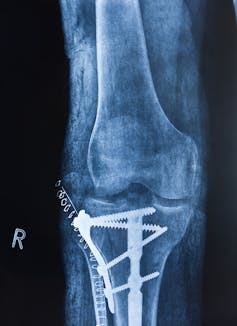

Manufacturing at or near the operating room is one example of a process that can be enabled with hybrid autonomous manufacturing. Often when patients with bone fractures undergo trauma surgery, metallic plates of varied shapes are required to hold bones together for healing. These are often created in the operating room, where the surgeon bends plates to fit the patient, sometimes using a 3D-printed model created from medical images of the patient as a form to bend the metal against.

Bending by hand is slow and imprecise, and stressing the plate in the wrong place can cause it to fracture. A robotic technician could cut and bend and finish a plate before surgery. Patients do better and save money if they spend less time in the hospital.